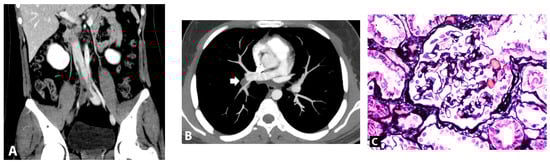

A 17-year-old man presented with three-day foamy urine and one-day right leg swelling and low-grade fever. He had received the first dose of mRNA SARS-CoV-2 vaccine (Pfizer/BioNTech BNT162b2) four days prior. Physical examination revealed non-pitting edema with a positive Homan sign on his right leg. He denied past medical illnesses, familial history of kidney and VTE, smoking, drug, and alcohol abuse. Initial laboratory revealed massive proteinuria (urine dipstick 4+ and 9.5 gm of 24-h urine protein), hypoalbuminemia (2.6 gm/dL), hypercholesterolemia (320 mg/dL), and lipiduria (positive oval fat bodies and fatty cats). His serum creatinine was 0.72 mg/dL. His nasal swab for SARS-CoV-2 by Real Time Polymerase Chain Reaction (RT-PCR) was negative. Two days after admission, the patient developed dyspnea without desaturation. A respiratory physical examination revealed normal and equal breath sounds. Chest X-ray was unremarkable. D-dimer was positive (>40,000 ng/mL). Duplex ultrasound demonstrated venous thrombosis of the right lower extremity veins (common femoral vein, saphenous vein, and popliteal vein). Computed tomography (CT) venography of the abdomen revealed thrombosis of the infrarenal inferior vena cava (IVC) extending to both iliac veins (Figure 1A) while CT pulmonary angiography demonstrated acute pulmonary embolism of the right main pulmonary artery, confirming a diagnosis of pulmonary embolism (Figure 1B). Low molecular weight heparin (enoxaparin at a dosage of 0.6 mL twice a day) was promptly started and was interrupted for 24 h for kidney biopsy a week later when the patient’s conditions of multiple thromboses were stable (e.g., no desaturation, unchanged left leg diameter). The kidney biopsy was performed revealing normal 18 glomeruli (Figure 1C) and tubulointerstitial structures with all immunofluorescent studies being negative, including IgM, IgG, IgA, C3, C1q, Kappa, and Lambda immunoglobulin light chain. Electron microscopy revealed diffused podocyte foot process effacement and microvillous transformation without electron dense deposit. The provisional diagnosis was MCD. To exclude secondary illnesses causing MCD, viral hepatitis profiles, treponemal, antinuclear, and anti-HIV antibodies were screened, and all turned out to be negative. According to VTE, the secondary causes other than MCD were also examined. His hemoglobin was 17.4 g/dL with negative JAK2 V617F mutation and a normal erythropoietin level of 20.5 mIU/mL (reference range 3.7–29.5 mIU/mL). Prothrombotic factors were measured; homocysteine 8.5 µmol/L (reference range 5–15 µmol/L), negative antiphospholipid antibodies (anti-beta 2 glycoprotein I IgM was 25 RU/mL at admission and 13 RU/mL at 12-week follow-up (reference range 0–20 RU/mL); inconclusive lupus anticoagulant at admission and negative at 12-week follow-up; and negative anti-cardiolipin IgM/IgG). Antithrombotic factors were also performed: antithrombin III activity 93% (reference range 79–112%), protein C activity 71% (reference range 70–140%), and protein S activity 109% (reference range 60–150%). The platelet factor 4 antibodies tested by ELISA-based assay revealed a negative result. The inflammatory marker of C-reactive protein (CRP) was 17.65 mg/L (reference range 0.3–5.0 mg/L). The complement levels were elevated: C3 248 mg/dL (reference range 100–233 mg/dL), C4 74 mg/dL (reference range 14–48 mg/dL), and CH50 > 51 U/mL (reference range 20–40 U/mL). One day after kidney biopsy, enoxaparin was resumed and prophylactic therapy with warfarin at dosage 7.5 mg daily was started. INR ranging 2.0–3.0 folds were maintained. Nephrotic syndrome subsided without any corticosteroids or immunosuppressive medications. 20 days post-admission, the patient’s right leg circumference gradually decreased, and the proteinuria significantly declined (0.3 gm/day) (Figure 2). The complete remission of MCD remained until a year after the onset of symptoms; there was no clinical or laboratory recurrence of MCD or clinically extensive thrombosis. The booster of SARS-CoV-2 vaccination was refused by the patient without subsequent experience of SARS-CoV-2 infection.

Figure 1. (A). Computed tomography showed partial thrombosis of the inferior vena cava and total occlusion of right iliac veins (asterisk). (B). Axial computed tomography pulmonary angiography image showed pulmonary embolism at the right descending pulmonary artery (arrow). (C). Kidney biopsy finding, light microscopy of glomerulus with Jone silver stain (original magnification, ×200) revealed normal glomerulus.